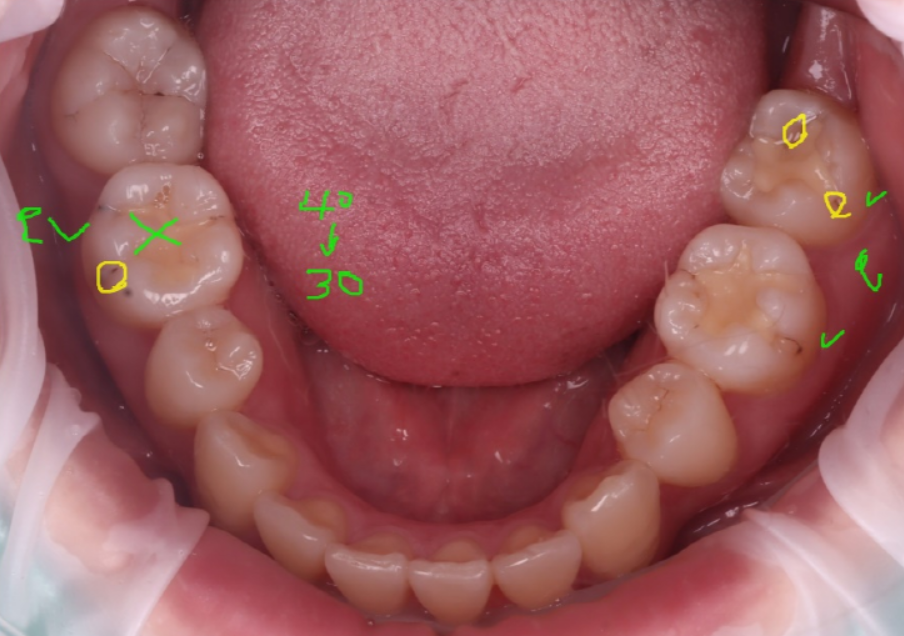

전체 구강을 살펴봤더니 왼쪽 제일 뒤어금니에도 충치가 있더라고요.

그래서 어금니(#27)도 같이 레진으로 치료하기로 했어요.